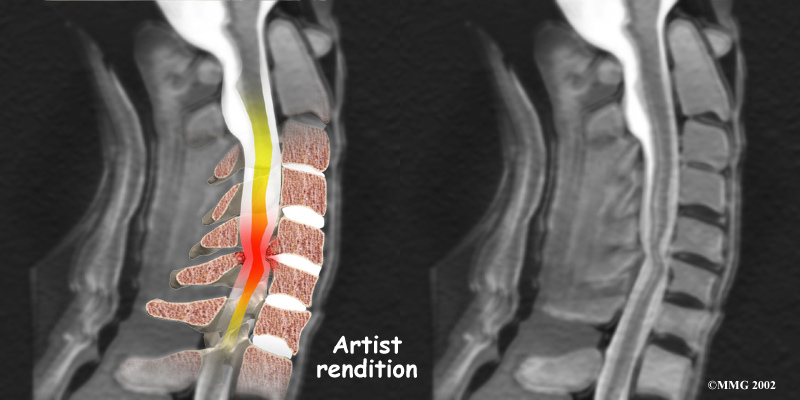

The nucleus may push through the weakened and torn annulus and into the spinal canal. This is called a herniated or ruptured disc. The disc material that squeezes out can press against the spinal nerves. The disc also emits enzymes and chemicals that produce inflammation. The combination of pressure on the nerves and inflammation caused by the chemicals released from the disc cause pain.

If the herniated disc material presses against a nerve root it can cause pain, numbness, and weakness in the area the nerve supplies. This condition is called cervical radiculopathy (mentioned earlier). And any time the herniated nucleus contacts tissues outside the damaged annulus, it releases chemicals that cause inflammation and pain. If the nucleus herniates completely through the annulus, it may squeeze against the spinal cord. This causes a condition that is even more serious because it affects all the nerves of the spinal cord. This condition is called cervical myelopathy.

Cervical Myelopathy

Stenosis means closed in. Spinal stenosis refers to a condition in which the spinal cord is closed in, or compressed, inside the tube of the spinal canal. Spinal stenosis may be caused by degenerative changes, such as bone spurs pushing against the spinal cord within the spinal canal.

Spinal Stenosis

However, stenosis can also develop when a person of any age has a disc herniation that pushes against the spinal canal. When the spinal cord is squeezed in the neck, doctors call the condition cervical myelopathy. This is an alarming condition that demands medical attention. Cervical myelopathy can cause problems with the bowels and bladder, change the way you walk, and affect your ability to use your fingers and hand.

The magnetic resonance imaging (MRI) scan uses magnetic waves to create pictures of the cervical spine in slices. The MRI scan shows the cervical spine bones, as well as the soft tissue structures such as the discs, joints, and nerves.

MRI scans are painless and don't require needles or dye. The MRI scan has become the most common test to look at the cervical spine after X-rays have been taken.